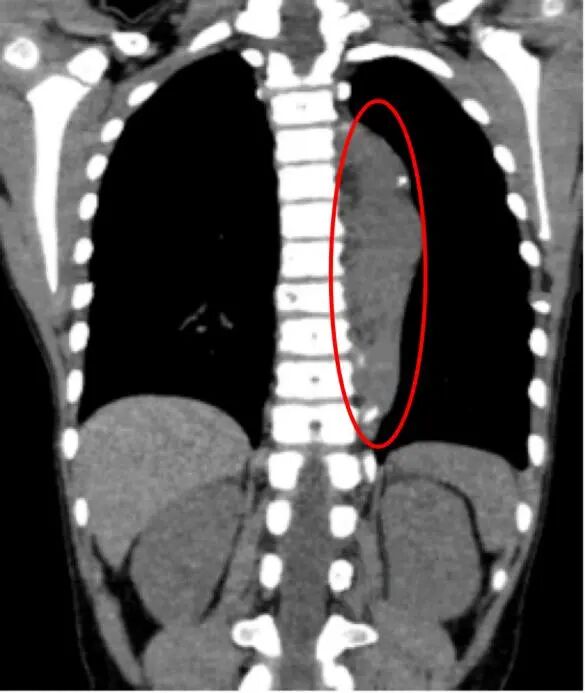

肿瘤位置极其凶险。肿瘤仍有约13厘米长,像一块“狗皮膏药”紧紧贴在孩子的脊柱旁,从胸腔顶部一直延伸到腰部,并且紧贴着人体最粗大的降主动脉。手术中稍有不慎,就可能引发致命性大出血。

术后

电钩沿肿瘤边界切开纵隔胸膜,再以钝锐交替的方式游离周围组织,精准离断进入病灶的动脉和静脉……终于,那个长达13厘米的肿瘤被完整切除!

手术成功了。

术后第7天,复查显示胸腔无积液、肺膨胀良好,浩浩顺利转入血液肿瘤科进行后续治疗。